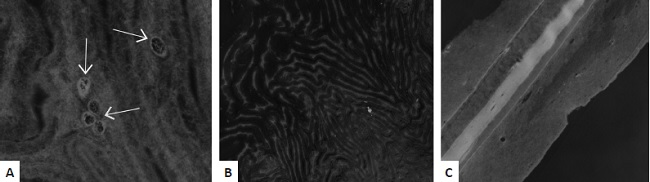

Microscopia eletrônica de transmissão foi feita para verificar o comportamento das células na membrana (Figura 1).